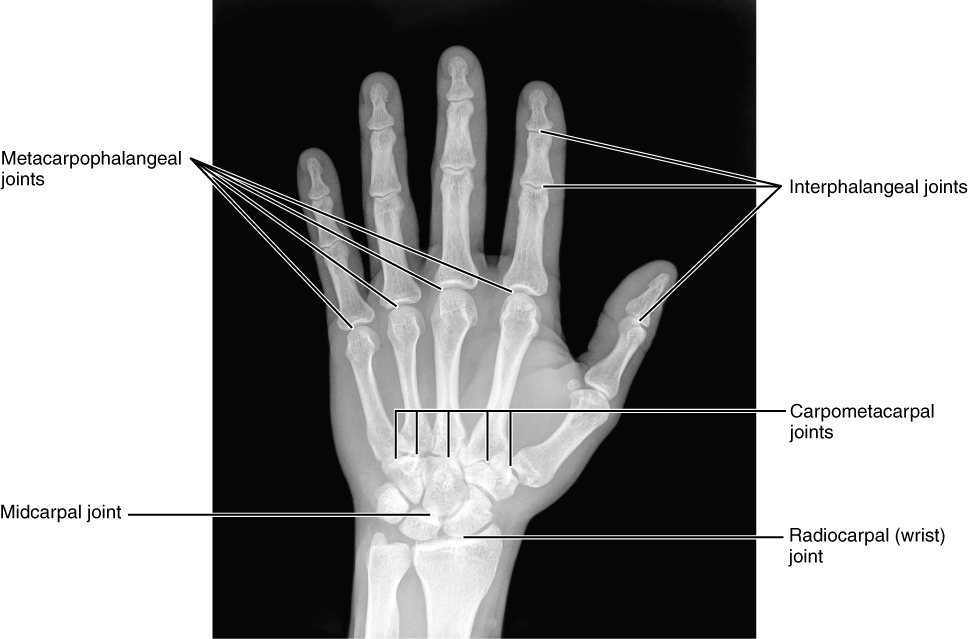

Figure 2.4 – Bones of the Hand: This radiograph shows the position of the bones within the hand. Note the carpal bones that form the base of the hand. (credit: modification of work by Trace Meek).

The carpal bones form the base of the hand. This can be seen in the radiograph (X-ray image) of the hand that shows the relationships of the hand bones to the skin creases of the hand (see Figure 2.4). Within the carpal bones, the four proximal bones are united to each other by ligaments to form a unit. Only three of these bones, the scaphoid, lunate, and triquetrum, contribute to the radiocarpal joint. The scaphoid and lunate bones articulate directly with the distal end of the radius, whereas the triquetrum bone articulates with a fibrocartilaginous pad (creating a space in the X-ray in Figure 2.4 between the ulna and the triquetrum). The distal end of the ulna thus does not directly articulate with any of the carpal bones.

The four distal carpal bones are also held together as a group by ligaments. The proximal and distal rows of carpal bones articulate with each other to form the midcarpal joint (see Figure 2.4). Together, the radiocarpal and midcarpal joints are responsible for all movements of the hand at the wrist. The distal carpal bones also articulate with the metacarpal bones of the hand.

The palm of the hand contains five elongated metacarpal bones. These bones lie between the carpal bones of the wrist and the bones of the fingers and thumb (see Figure 2.3). The proximal end of each metacarpal bone articulates with one of the distal carpal bones. Each of these articulations is a carpometacarpal joint (see Figure 2.4). The expanded distal end of each metacarpal bone articulates at the metacarpophalangeal joint with the proximal phalanx bone of the thumb or one of the fingers. The distal end also forms the knuckles of the hand, at the base of the fingers. The metacarpal bones are numbered 1–5, beginning at the thumb.

The fingers and thumb contain 14 bones, each of which is called a phalanx bone (plural = phalanges), named after the ancient Greek phalanx (a rectangular block of soldiers). The thumb (pollex) is digit number 1 and has two phalanges, a proximal phalanx, and a distal phalanx bone (see Figure 2.3). Digits 2 (index finger) through 5 (little finger) have three phalanges each, called the proximal, middle, and distal phalanx bones. An interphalangeal joint is one of the articulations between adjacent phalanges of the digits (see Figure 2.4).